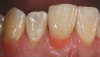

Fig 19. A small, synthetic velvet mini buff disc and polishing paste were used to impart a predictable luster to the gingival restorations.

Figure 19

Fig 20. Postoperative view of the completed composite restorations provided to treat “the absence of pink.” Note that this gingival prosthetic solution is repairable, non-invasive, and cost-effective for patients.

Figure 20